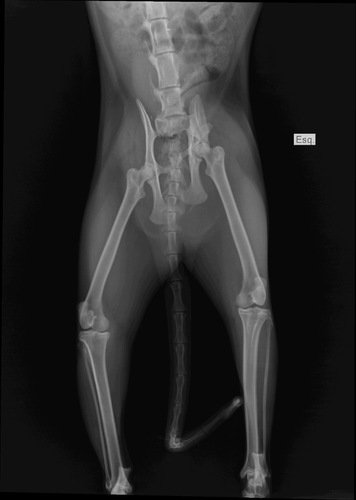

Preciso arrecadar esse valor para realizar a cirurgia da Cora! Ela caiu do 6° andar e precisa da cirurgia com urgência para poder defecar e urinar, pois quebrou o osso da pélvis e teve uma luxação!